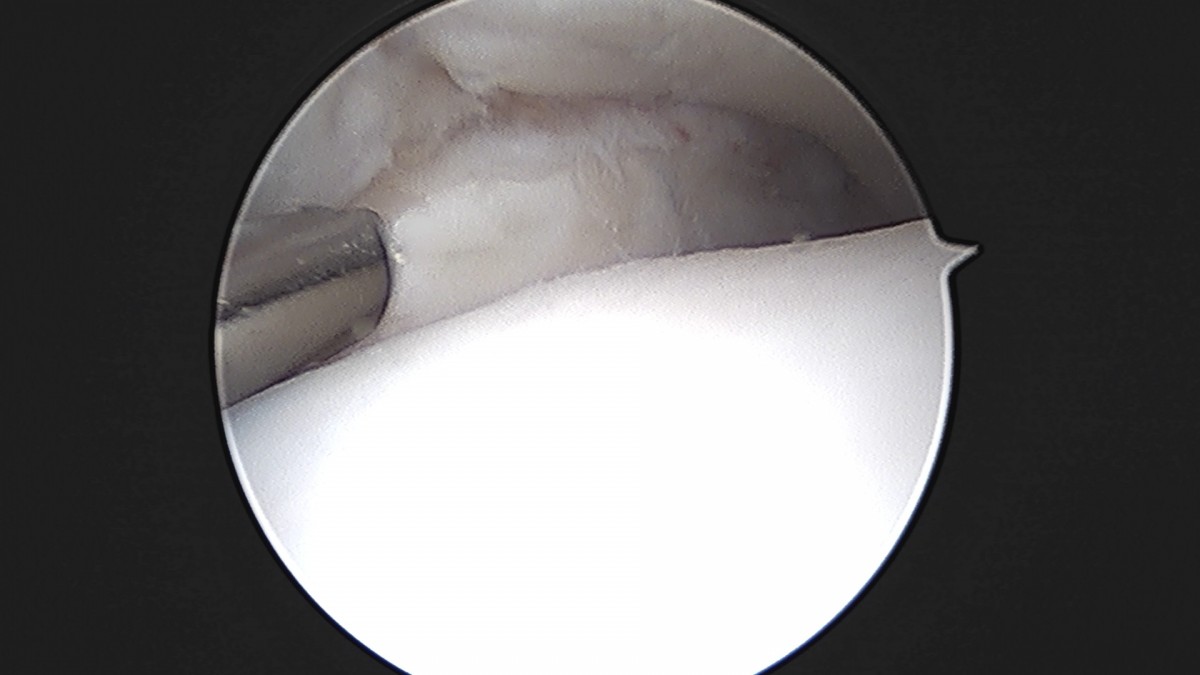

이재상원장님 발목 인대 봉합술 이지O 환자

작성자 최고관리자 댓글 0건 조회 681회 작성일 25-09-16 16:26